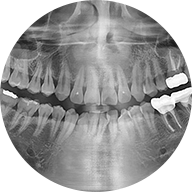

대학병원에 가지 않으셔도

구미이튼 365치과에서

조직검사

및 소수술을 받아보세요.

구미이튼 365치과에서는

서울대학병원 구강병리과와 협업하여

큰 병원에 가실 필요없이,

구미에서 과정 그대로 소수술 및

조직검사를

시행하고 있습니다.